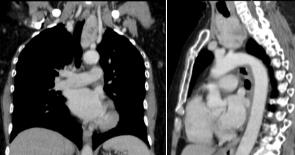

Paciente femenino de 64 años quien inicia enfermedad actual 3 meses previo ingreso cuando presenta disnea progresiva de grandes a moderados esfuerzos asociado a tos seca no productiva intermitente y disfagia leve a sólidos, motivo por el cual acude y se evalúa. Al examen físico presenta signos vitales estables, cuello móvil con una tiroides no visible ni palpable (Figura 1), sin adenomegalias. Tórax simétrico normo expansible, ruidos respiratorios presentes en ambos hemitórax sin agregados. Resto del examen físico anodino. Exámenes de laboratorio incluyendo prueba de COVID sin alteraciones. En la radiografía de tórax se evidencia discreta desviación de la tráquea hacia la derecha, parénquima pulmonar sin alteraciones. Se realiza Tomografía (TC) de cuello y tórax evidenciando LOE a nivel de mediastino anterior en estrecha relación con los grandes vasos torácicos y con aparente continuidad con la glándula tiroides (Figura 2). Se realiza posteriormente eco tiroideo el cual se concluye como una glándula tiroidea aumentada de tamaño, asimétrica a predominio de lóbulo izquierdo en relación a bocio multinodular (tirads 3). Perfil tiroideo sin alteraciones. Se decide llevar a mesa operatoria obteniendo como hallazgos una glándula tiroidea aumentada de tamaño a predominio de lóbulo izquierdo, el cual se encontraba ocupando casi la totalidad del mediastino anterior (Figura 3). Se logra realizar tiroidectomía total por vía transcervical, egresando sin complicaciones al tercer día de posoperatorio. El diagnóstico histopatológico final fue una hiperplasia multinodular difusa, sin evidencia de atipias.